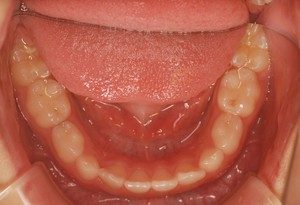

2011年10月24日 Y'sブログ 2022年10月25日 浜田山ワイズ歯科 矯正歯科 おとなの歯が乳歯の後ろから生えてきましたその5 その4や今回のような『スペース不足』のケースでは、タイミング良くちょっとした手助けを施してあげることで、永久歯が綺麗に整列します。 下の写真は、上の写真の状態から『ちょっとした手助け』を得て、理想的な歯並び・発育へ軌道修正した現在9歳の男の…